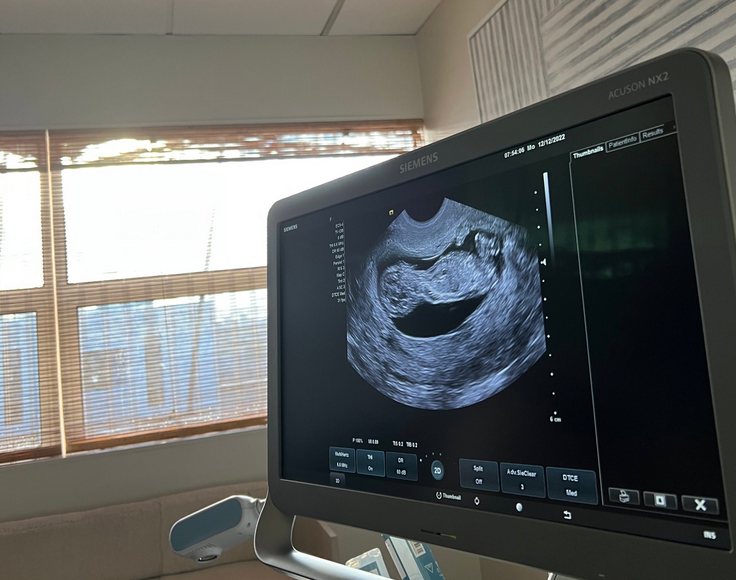

祝・妊娠

今回自身のSNSを通して発表したのは妊娠の知らせです。

メッセージと共にエコー写真を投稿しました。